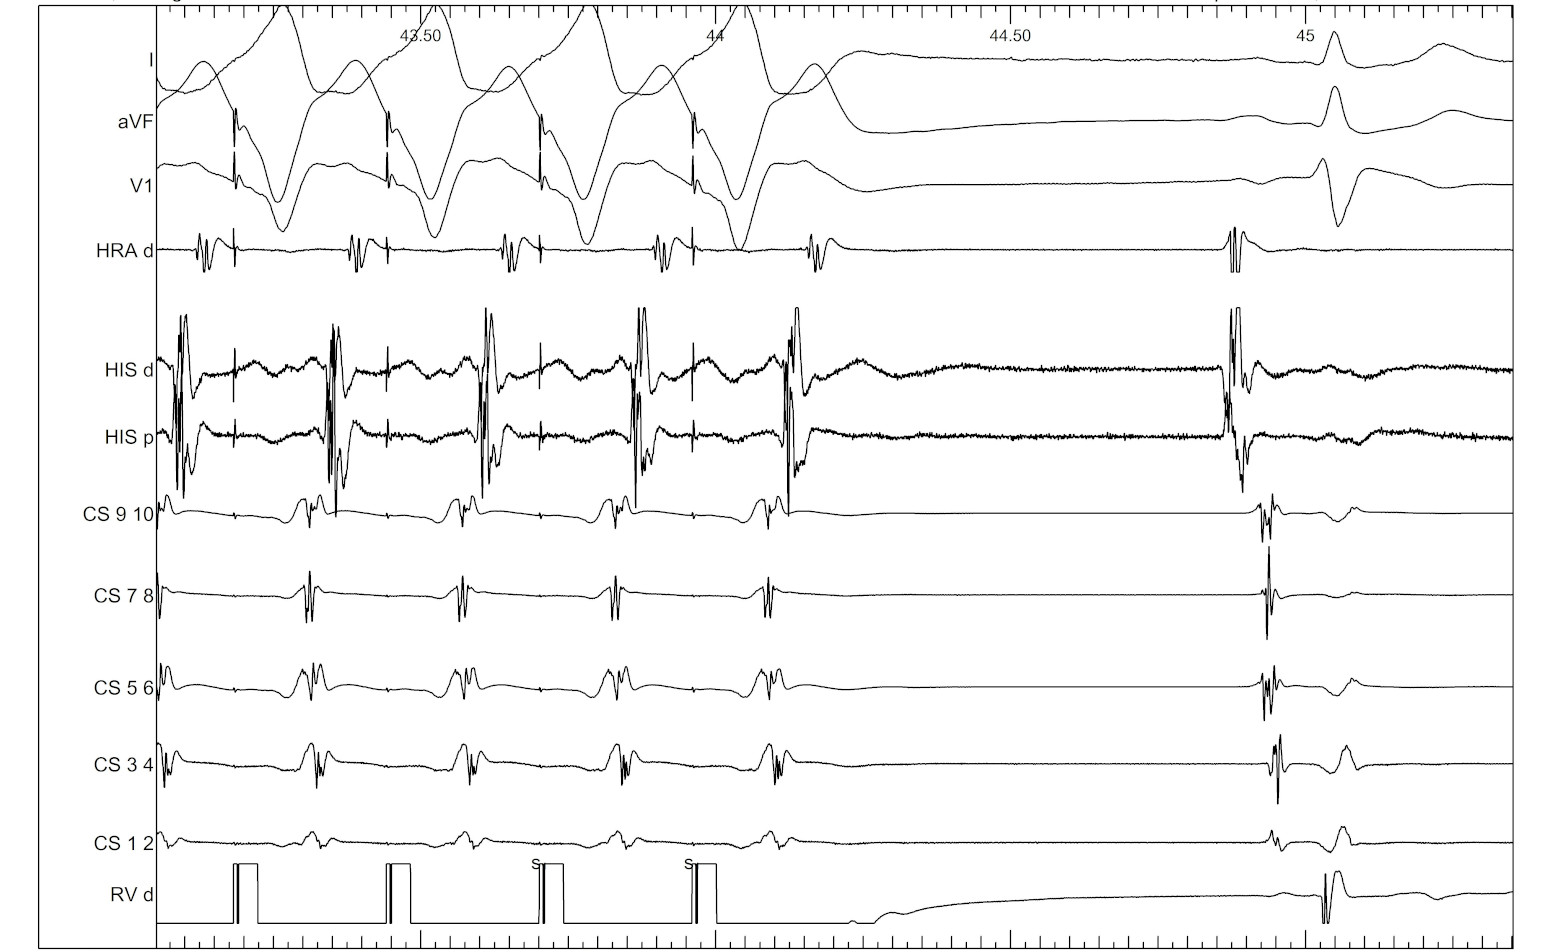

Termination during VOP - What now ?

vop_termination.jpg

Onset of VOP

vop_onset.jpg